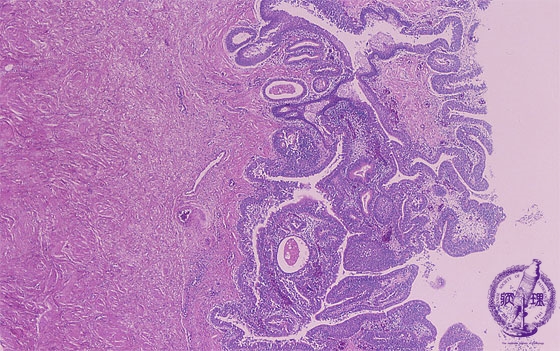

Microscopic findings (HE, high power view): Cystitis glandularis. The urothelial (transitional epithelial) cells present glandular metaplasia. The epithelia form cystic dilated space to form a gland-like space. Occasionally, these spaces contain mucus materials.